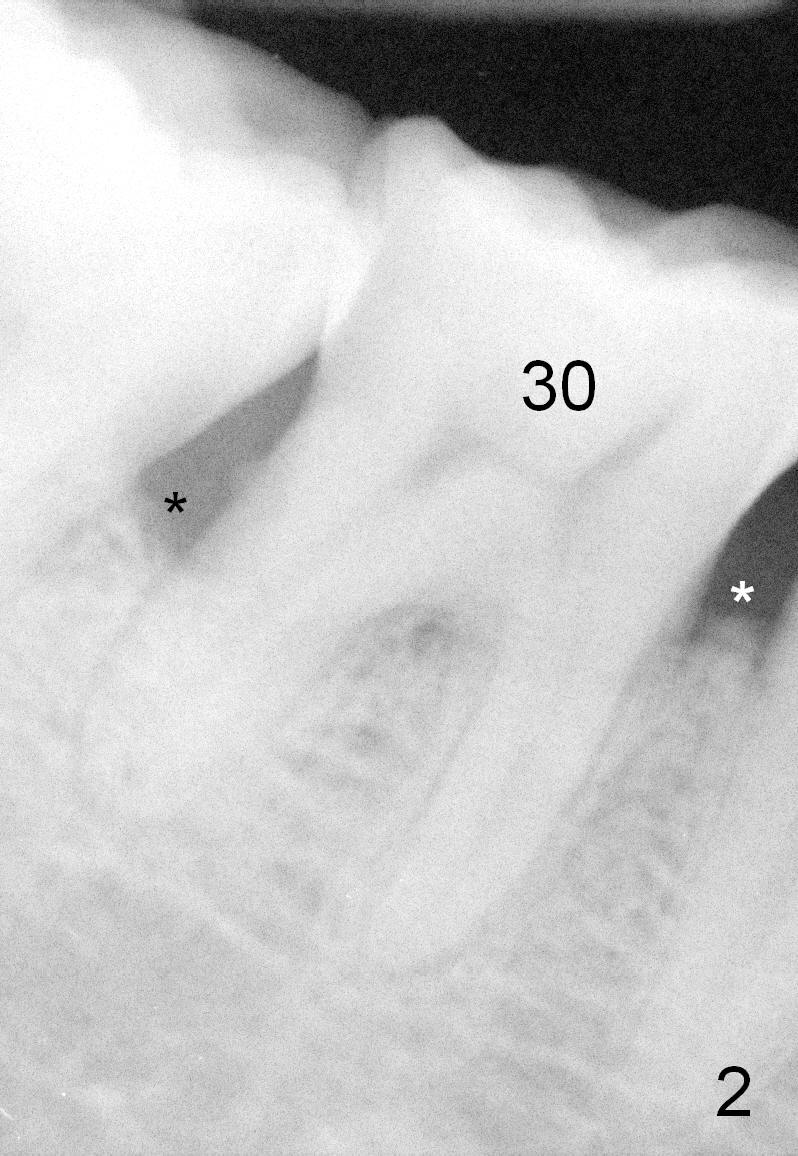

One year and a half years ago, the tooth #31 of a 48-year-old man had infection (Fig.1 *) and was extracted without implant.  There was more bone loss in the distal of #30 than in the mesial (Fig.2 *).  Recently the patient returns with infection at #30 distally with severe bone loss (Fig.3 *).  An immediate implant is to be placed mainly in the mesial socket (Fig.4 (bone-level), Fig.5 (tissue-level)).